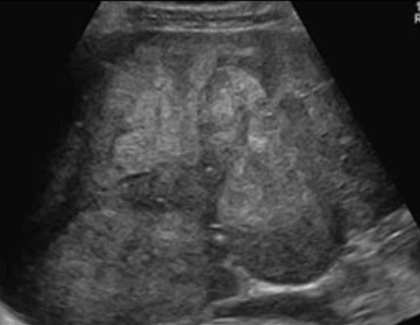

2~3cm hcc sono features ③ 3~5 cm hcc sono finding

- hypo-hyperechoic

- heterogenous

- irregular

- hump sign (표면에 존재하는 결절형 종괴에서 간표면으로 종괴가 돌출하는 경우 나타난다)

- mosaic pattern (종양내부에 괴사나 출혈이 생겨 내부에 균열이 있는 것처럼 보이는 모자이크패턴이 나타남)

- color doppler : internal mass pattern (feeding artery)